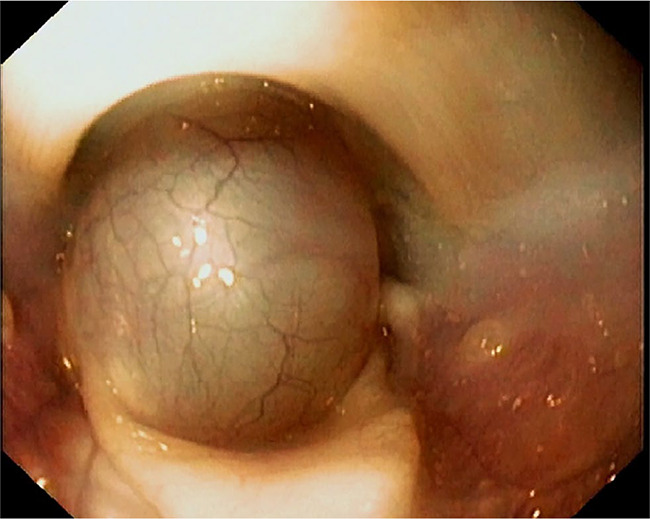

Case summary: An 8-month-old spayed female cat presented with a 7-week history of progressive dyspnoea, dysphagia and regurgitation. Plain radiography revealed megaoesophagus with a large, rounded, soft tissue opacity laryngeal mass. Endoscopic examination revealed a fluid-filled lesion, which was lanced and drained completely. As a result of recurrence of the mass and infection 2 days later, the mass was surgically excised. The mass was diagnosed as a laryngomucocele based on clinical and histopathological findings. Clinical signs resolved immediately after removal of the mass, the megaoesophagus resolved a couple of days postoperatively and no relapse was noted over the following 3 years.